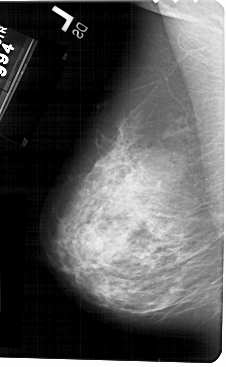

A_1511_1.LEFT_CC

LEFT_CC LINES 5491 PIXELS_PER_LINE 3271 BITS_PER_PIXEL 12 RESOLUTION 43.5 NON_OVERLAY